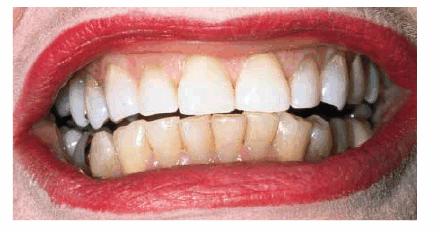

Figures 29-5A and B show a patient who did not like the

appearance of her front teeth. She felt that her maxillary central incisors

were too dark and too short. Cosmetic resin bonding was chosen as the treatment

of choice because of the immediacy of the result. Figures 29-5C and D show how the teeth were both lightened

and lengthened to provide a younger-looking smile line.

Figure 29-5A and B: This 78-year-old lady had shortened and darkened maxillary central incisors. (Reproduced with permission from Goldstein RE. Change your smile. 3rd edn. Carol Stream, IL: Quintessence, 1997:242.)

Figure 29-5C and D: Composite resin bonding was done to lengthen and lighten the central incisors. (Reproduced with permission from Goldstein RE. Change your smile. 3rd edn. Carol Stream, IL: Quintessence, 1997:242.)